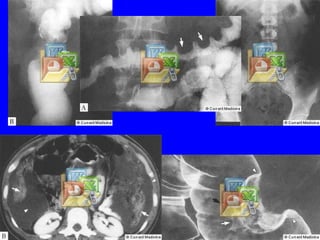

Estudio radiológico del colon por enema de bario. Placa de repleción.

Estudio radiológico del colon por enema de bario. Placa postevacuación.

Estudio radiológico delcolon por enema de bario. Placa de repleción.

Estudio radiológico delcolon por enema de bario. Placa postevacuación.